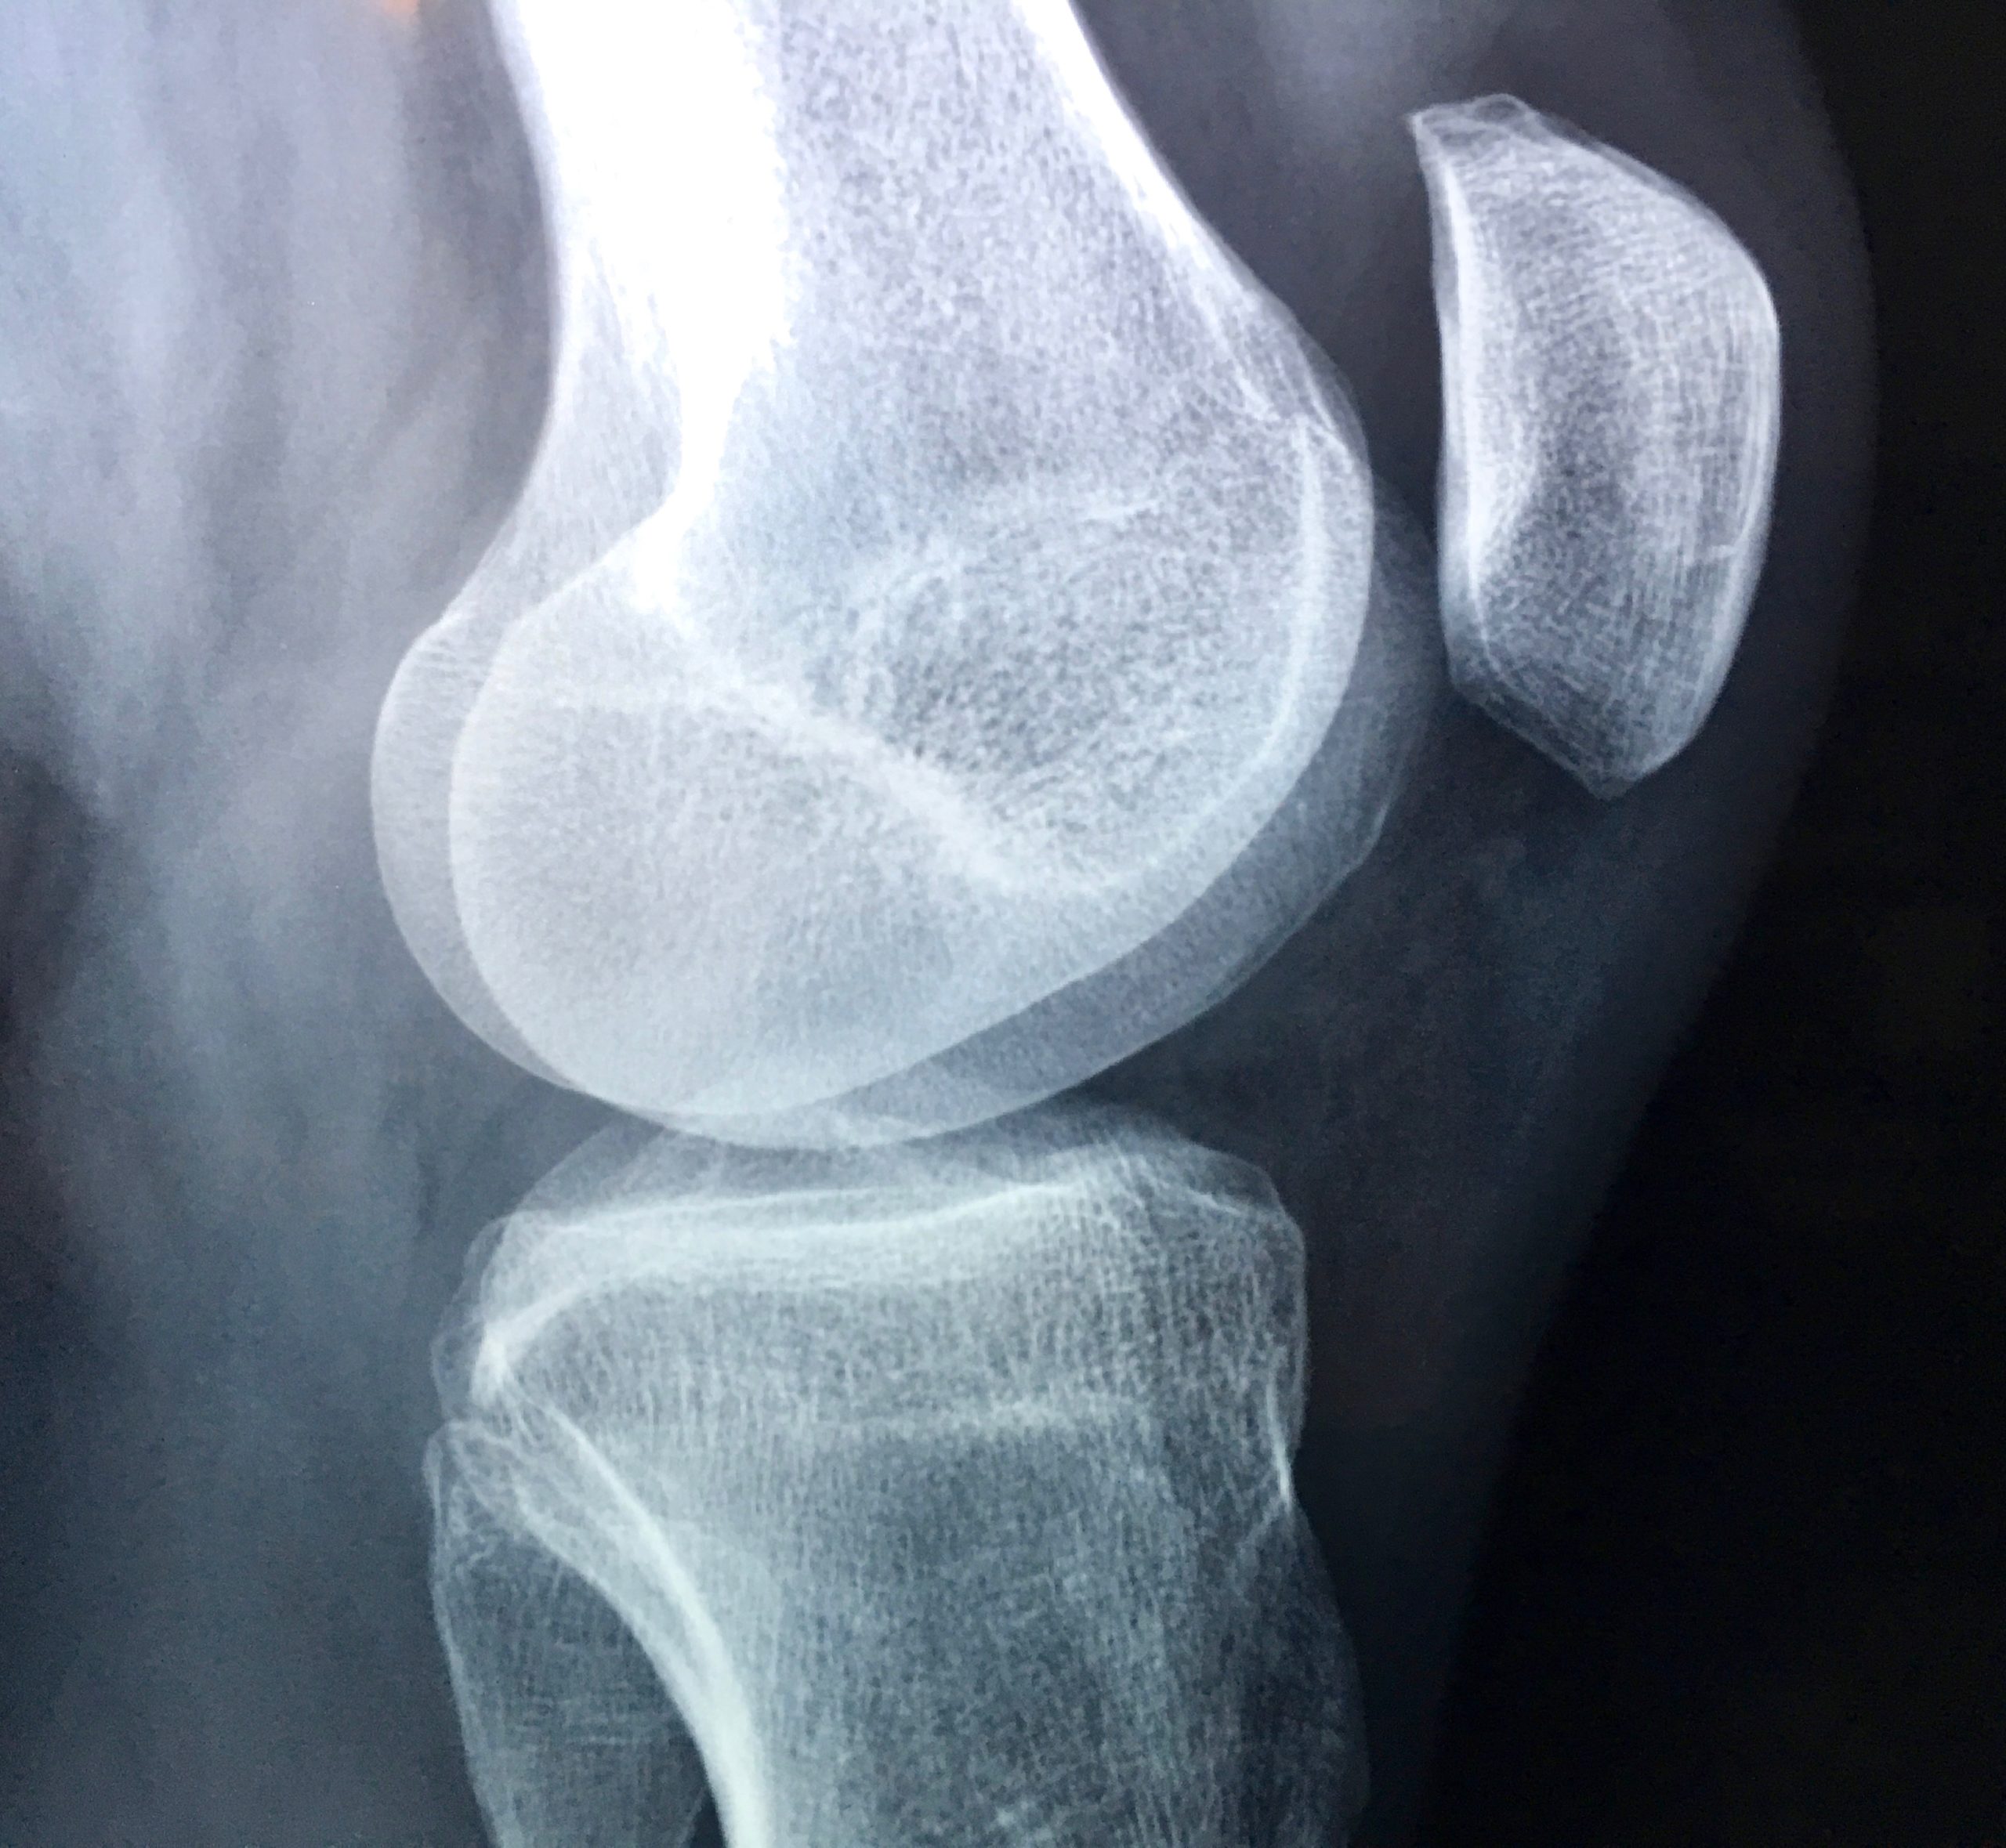

However for some, knees or hips may have deteriorated past the point of no return to where surgical intervention  the only realistic option. If this surgery is inevitable there are ways to improve your experience of it and your outcomes.

After surgery there will be stages of scar tissue and the rebuilding of tissues as you heal. Plus a gradual process of regaining weight-bearing and movement. Even with an exercise programme, full ranges of motion and strength and whole-body coordination may not be reached. Structural compensations often develop post-surgery, affecting posture, balance, walking gait and whole-body movement.